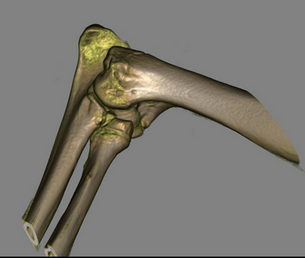

3D Print service :

20220801_090606